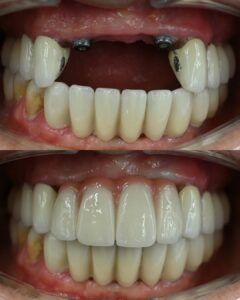

I assist my patients in my clinic in Istanbul/Turkey on Gum Diseases, Surgeries and Dental Implant Treatments.